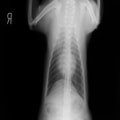

A:胸部レントゲン写真 正面像

胸部レントゲン検査において重度の心拡大と肺水腫が認められた。超音波検査では、重度の僧帽弁閉鎖不全症、三尖弁閉鎖不全症、中程度の大動脈弁閉鎖不全症を合併していることが判明した。三尖弁逆流速度から肺高血圧症が示唆された。

ACE阻害薬、ピモベンダン、硝酸イソソルビド徐放剤、ベラプロストナトリウム、利尿剤としてフロセミドとスピロノラクトンを用いて治療を行った。